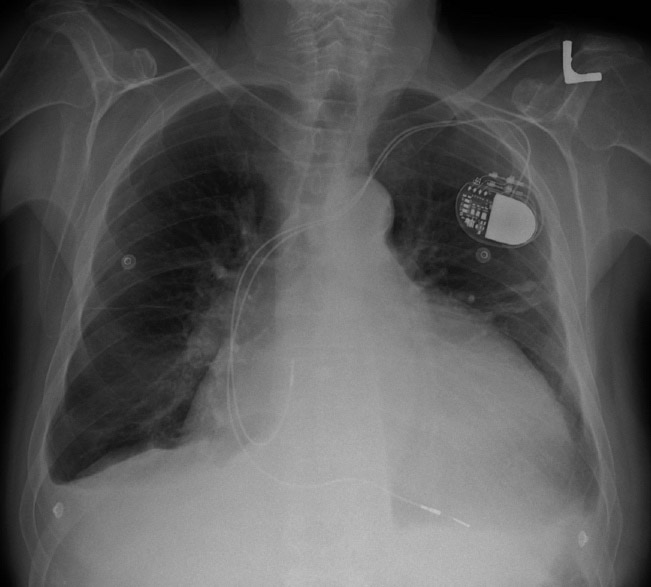

Cardiomegaly is often detected on an anterior-posterior chest x-ray (AP CXR). The standard method for measuring heart size on AP CXR is known as the Danzer Method, and it involves measuring the distance from the midline of the spine to the most lateral aspect of the cardiac apex (distance B, in the image below), and adding this distance to that found from the same midline to the most lateral aspect of the right atrium (distance A). This number is then divided by the largest horizontal width of the chest (distance C), from right to left pleural surface (usually found just above the left hemidiaphragmatic surface). This value (A+B/C) is known as the cardiothoracic ratio (CTR). A CTR > 0.5 indicates cardiomegaly.

Image obtained from the Creative Commons database.